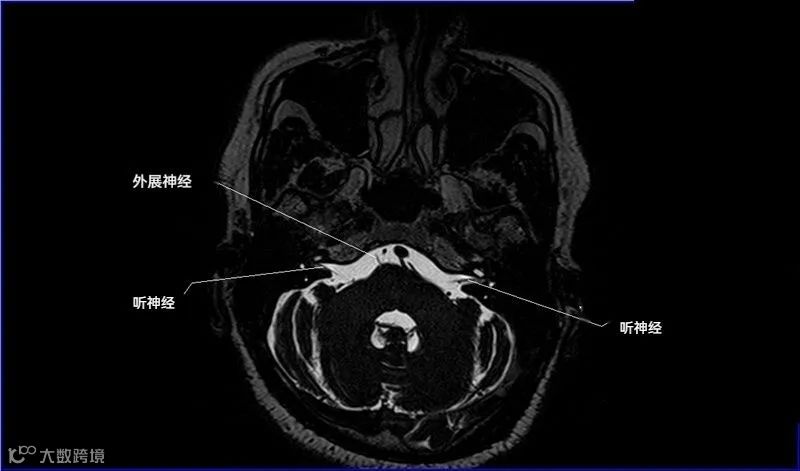

十二对脑神经口诀

一嗅二视三动眼,四滑五叉六外展,

七面八听九舌咽,迷走及副舌下全。